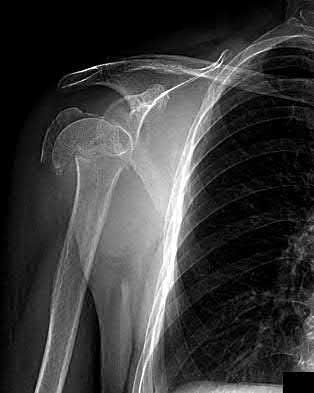

2. # A 35-year-old woman is involved in a head-on collision while driving. Initial radiographs are shown in Figures 8a and 8b. Injury to what vessel increases the risk for osteonecrosis of the injured bone?

1. Dorsalis pedis artery

2. Perforating peroneal artery

3. Lateral tarsal artery

4. Artery of the tarsal canal

5. Artery of the tarsal sinus Corrent answer: 4

The patient has a Hawkins type III talar neck fracture-dislocation with a risk of osteonecrosis ranging from 69% to 100%. Anatomic studies have shown that the artery of the tarsal canal supplies the lateral two thirds of the talar body.

The other vessels listed provide no significant contribution to the talus.